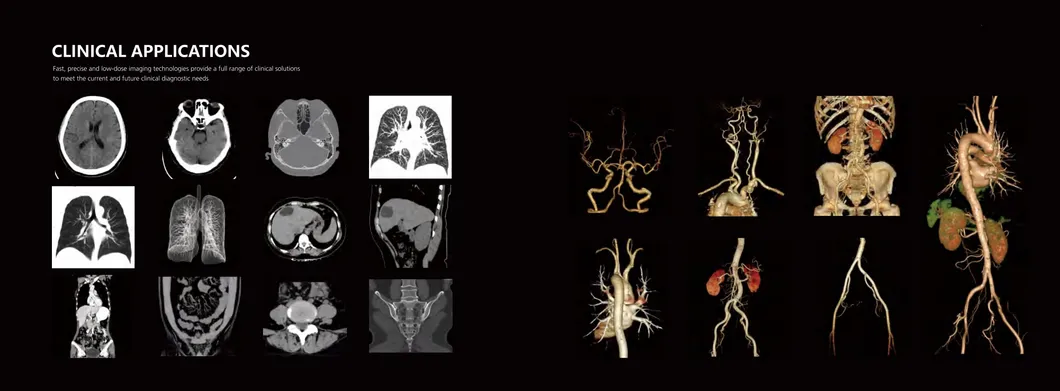

The system provides advanced intelligent scanning capabilities for precise medical diagnosis. Featuring high-performance imaging technology, it ensures clarity and accuracy in various clinical applications.